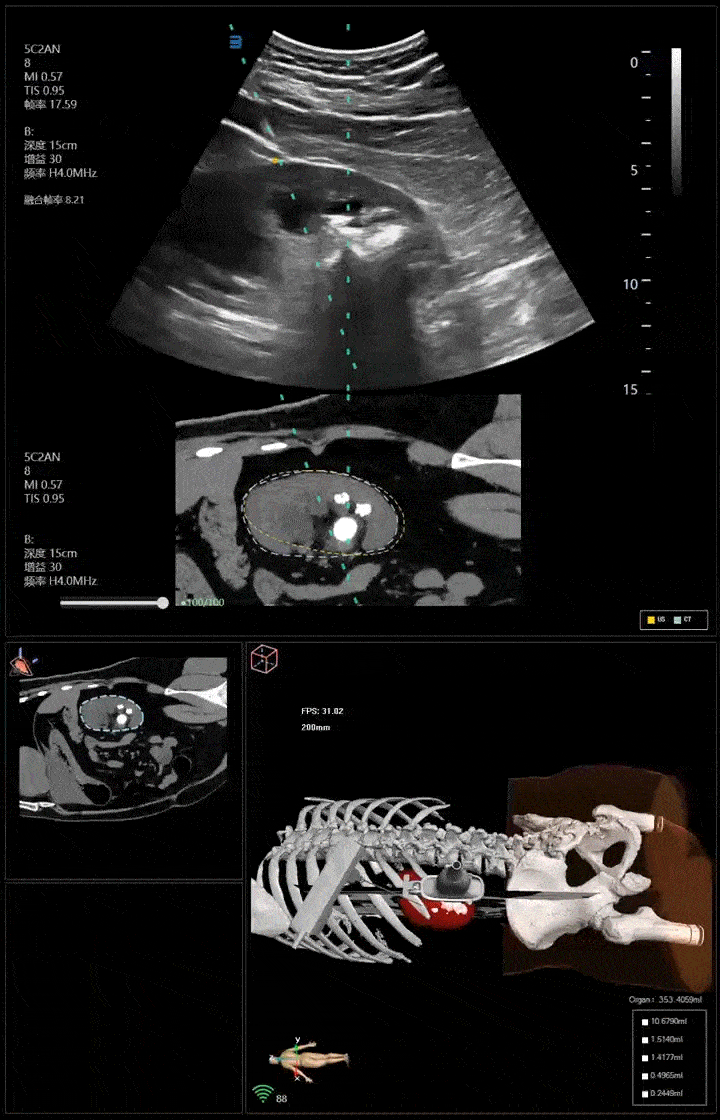

卡本医疗携自主研发的VENUS AI多模态影像融合精准介入平台亮相,以影像融合、人工智能等前沿技术助力泌尿结石精准诊疗,引发与会专家高度关注。

以VENUS为代表的国产医疗设备,打破了传统影像组学技术以及认知融合本身的思维局限性,实现了结石诊疗领域的突破性技术进展。VENUS的弹性形变场技术可以有效解决器官位移及形变问题,减少误差;2D高清融合影像与3D立体人体解剖结构实现了可视化的影像联动,带来了更强透视感、更高配准度的手术视野以及更加精准的靶向引导手术操作体验,为临床诊疗与科研提供了诊疗利器。

程帆教授、周密教授表示,从临床实践来看,VENUS的前沿技术应用成果显著。它不仅大幅度提高了单次穿刺的成功率,降低出血风险,缩短患者住院天数;同时,还减少了通道建立时间,提高了手术即刻清石率,减少二期手术的可能性,减轻了患者的负担。